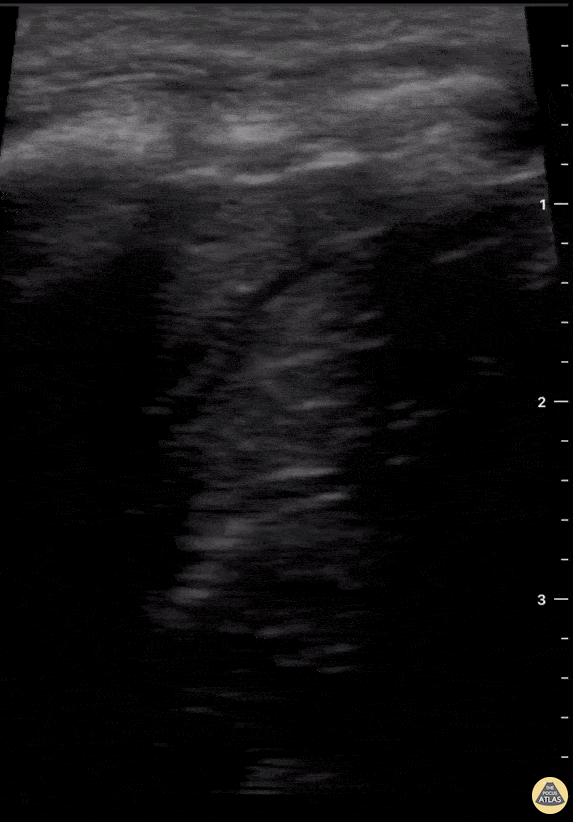

2 yr old child with sudden respiratory distress with O2sat 70%. Child was intubated in prehospital setting by a HEMS physician and POCUS obtained en route to the hospital revealed a completely collapsed (atelectatic) left lung as seen in the clip; right lung was normal. In hospital an aspirated foreign body (a raisin) was removed a from the child’s left main bronchus. Child made a full recovery. Victor Viersen @victor_viersen